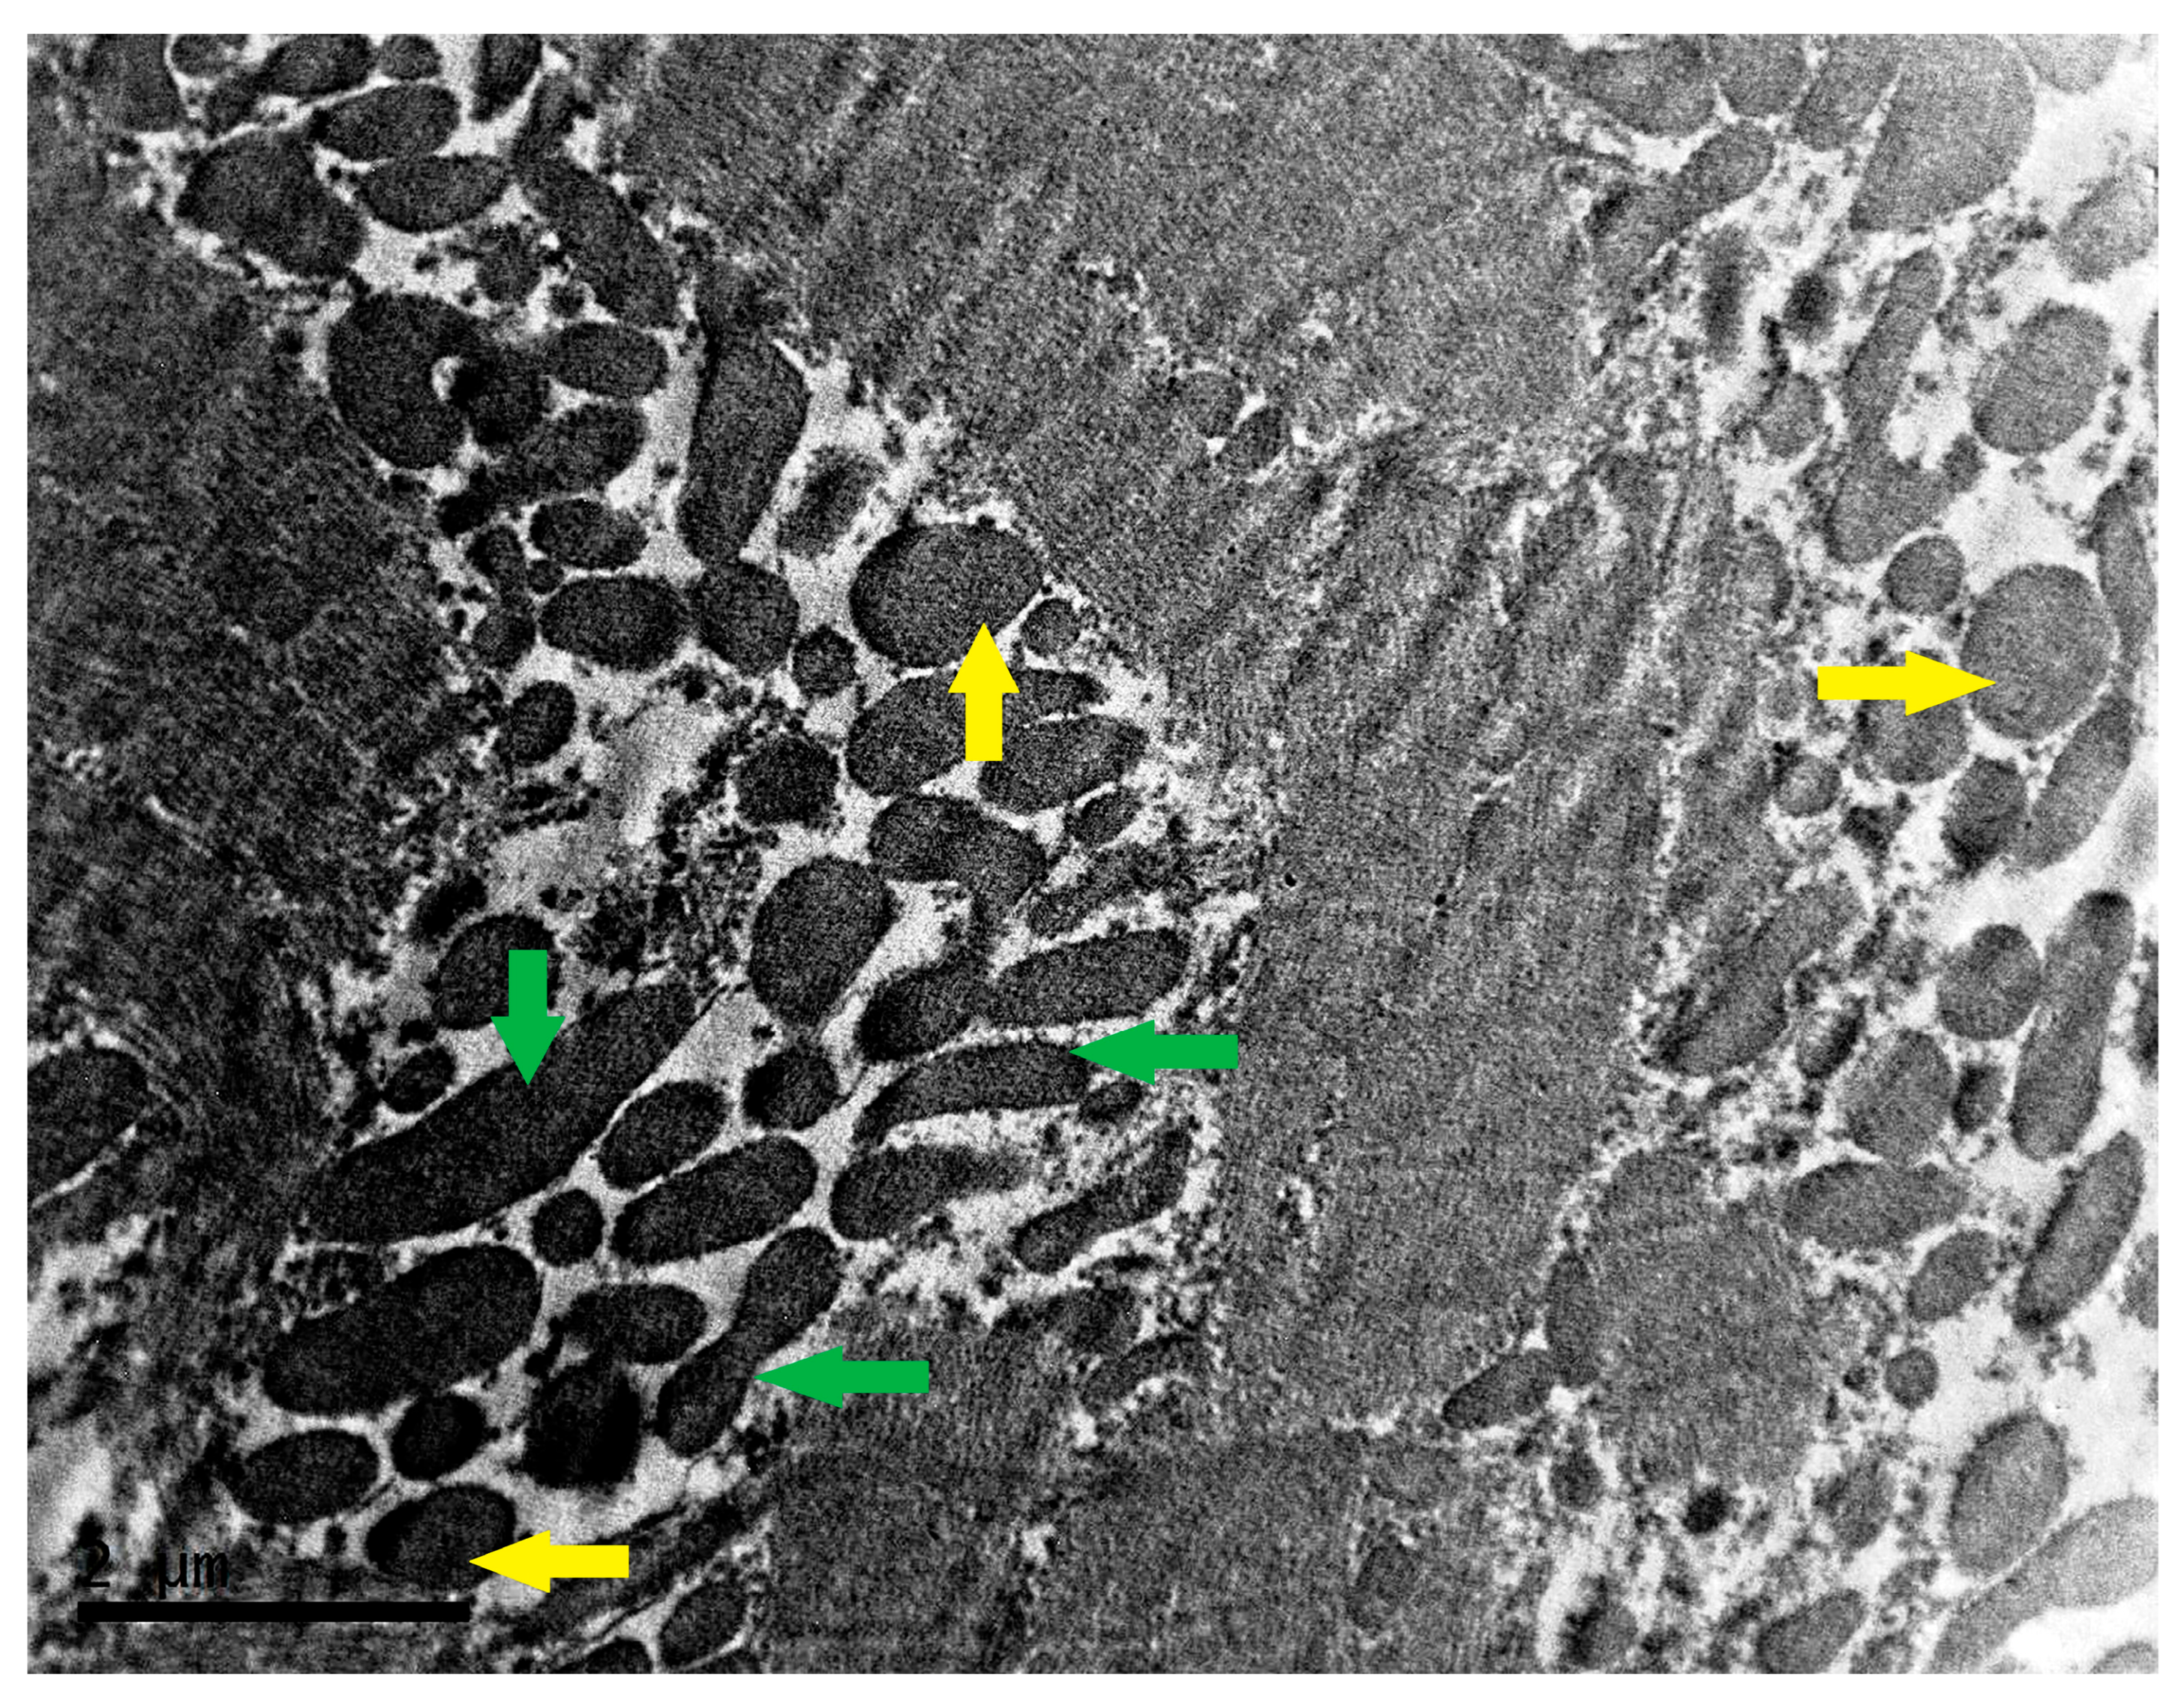

- Nollet, E.E.; Duursma, I.; Rozenbaum, A.; Eggelbusch, M.; Wüst, R.C.I.; Schoonvelde, S.A.C.; Michels, M.; Jansen, M.; van der Wel, N.N.; Bedi, K.C.; et al. Mitochondrial dysfunction in human hypertrophic cardiomyopathy is linked to cardiomyocyte architecture disruption and corrected by improving NADH-driven mitochondrial respiration. Eur. Heart J. 2023, 44, 1170–1185. [Google Scholar] [CrossRef]